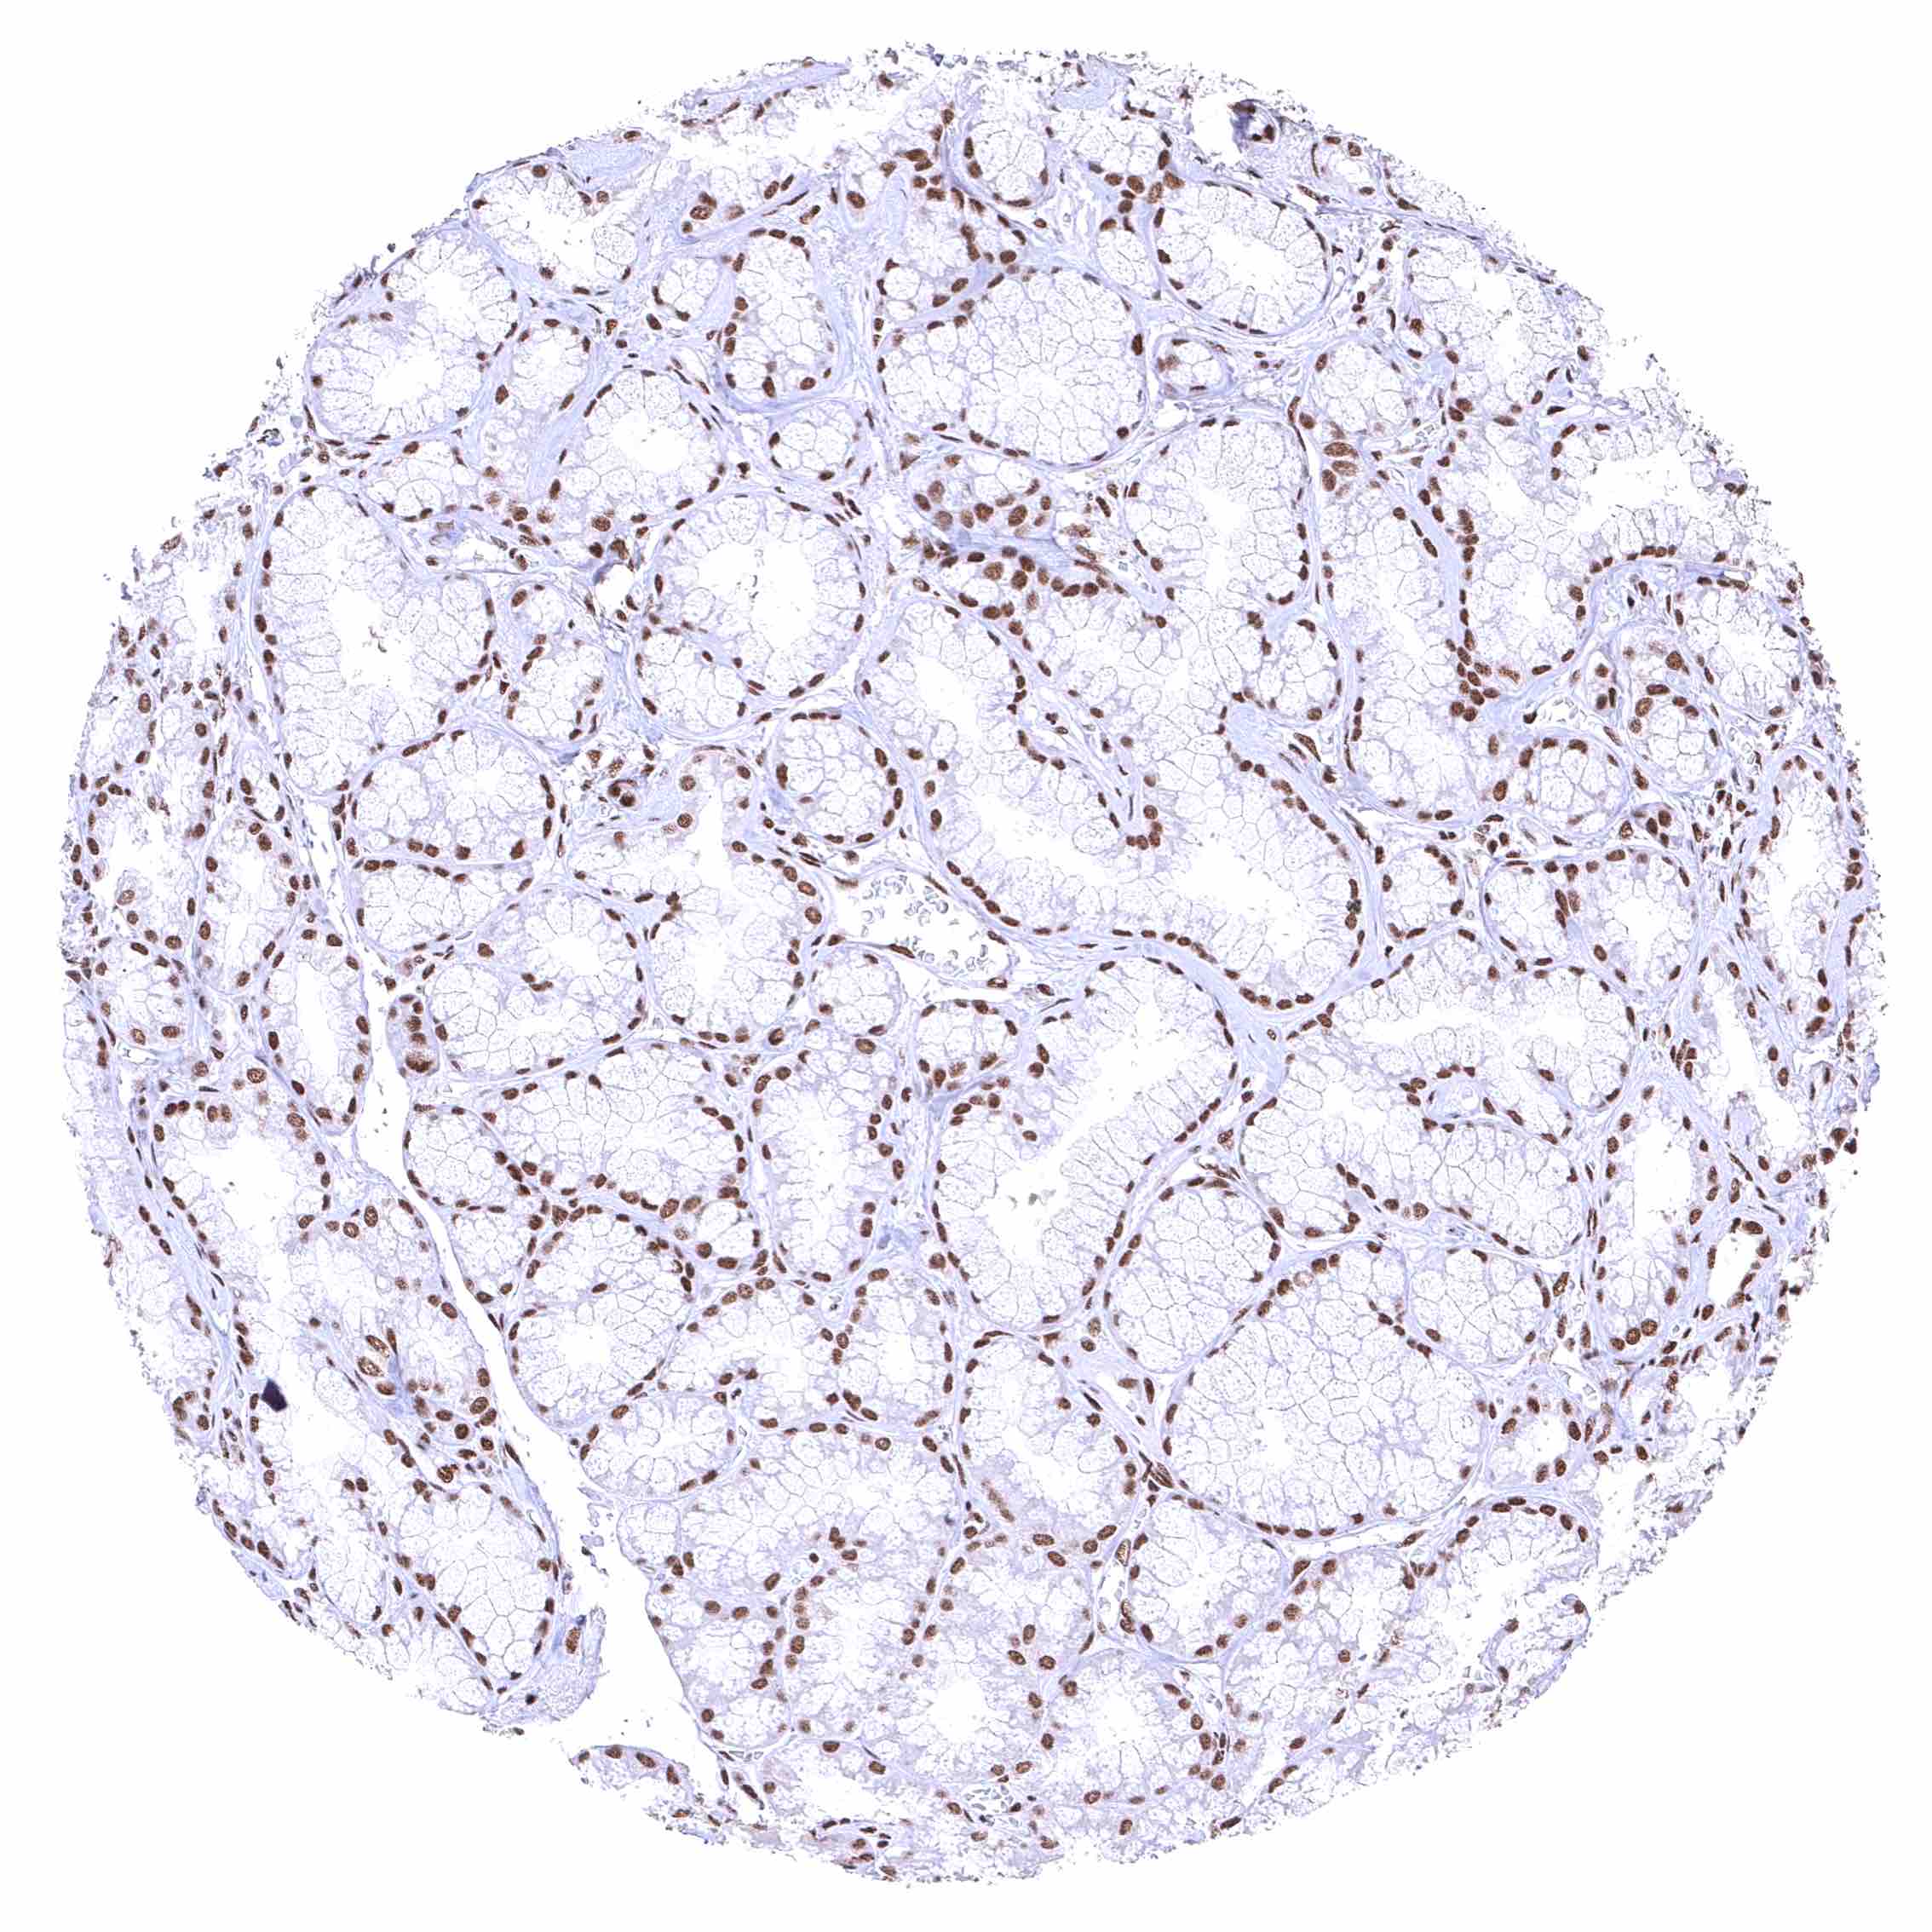

Placenta, mature – BRD4 staining is either absent or massively reduced in the syncytiotrophoblast.